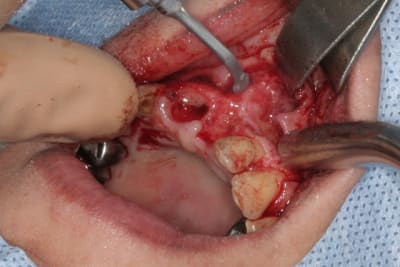

un autre cas EII MCI sur 11/21...mais en photos (j'ai aussi la vidéo, faut que je la passe sur youtube)

1 t869zn - Eugenol

2 v0ltek - Eugenol

3 rz5ncz - Eugenol

4 k166af - Eugenol

5 gkyzlc - Eugenol

6 fb5vql - Eugenol